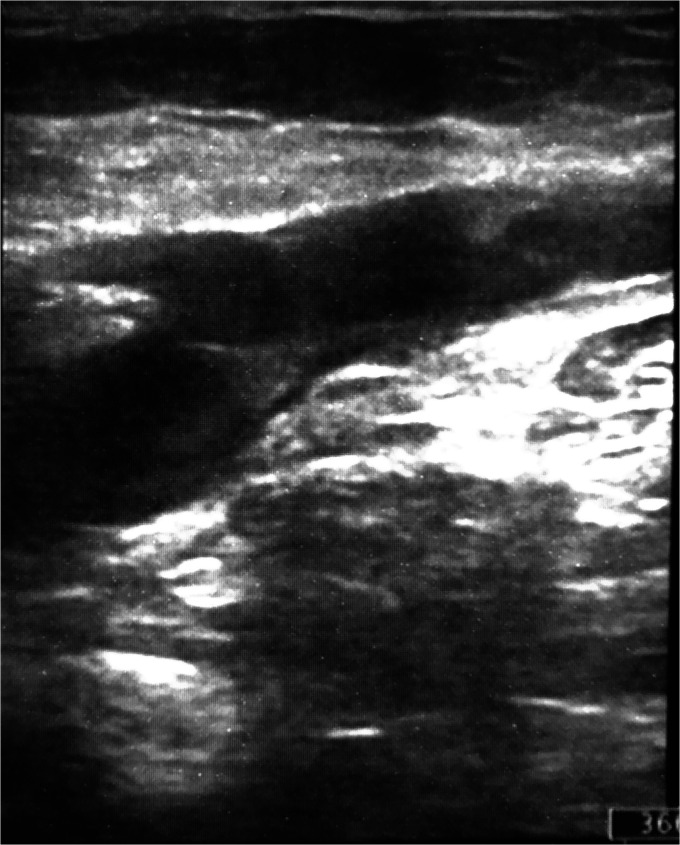

股总静脉浮静脉血栓具有肺动脉栓塞的高潜在风险。临床治疗,使用抗凝剂或纤溶剂,开放血栓切除术,或血管内装置血栓切除术都已被使用。我们的病例描述了一名肥胖患者,他受到来自GSV的漂浮血栓的影响,并潜入股总静脉,通过联合临时腔静脉插入和开放手术取栓成功治疗。

The floating venous thrombus in the common femoral vein has a high potential risk for pulmonary embolization. Clinical treatments, using anticoagulants or fibrinolytic, open thrombectomies, or thrombectomies by endovascular devices have all been used. Our case describe an obese patient affected by floating thrombus coming from GSV and diving in common femoral vein successful treated by combined both temporary vena cava insertion and open surgical thrombectomy.